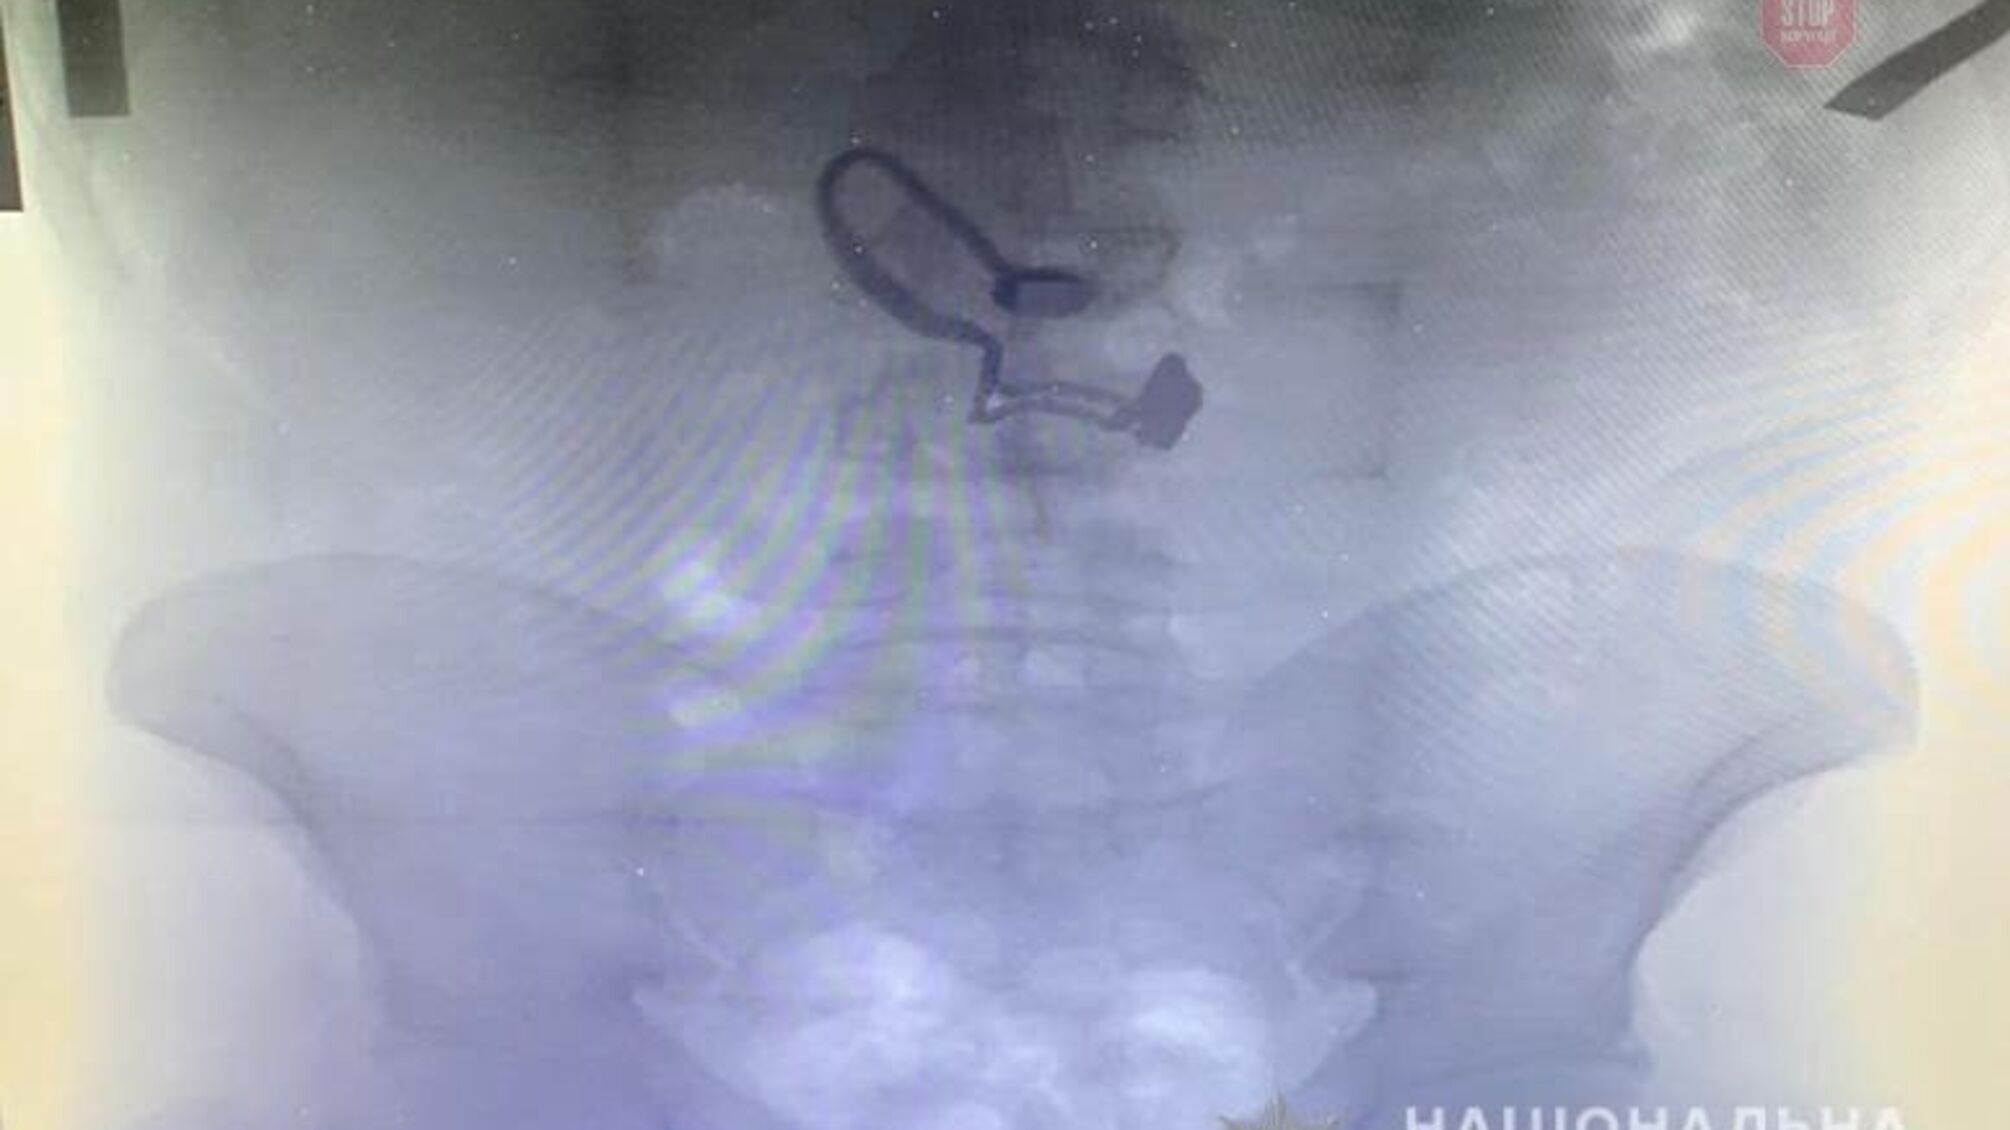

У чоловіка був знайдений гаманець потерпілої. Згодом він зізнався правоохоронцям, що зірваний ланцюжок проковтнув. Під час медогляду на рентген знімку затриманого лікарі виявили прикрасу.